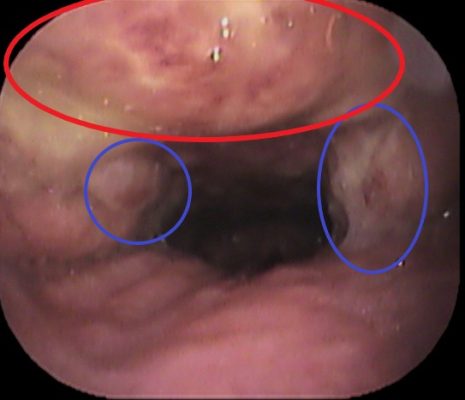

ファイバーを奥まですすめると![]()

採血データでも炎症反応を認めました(赤丸部分)。